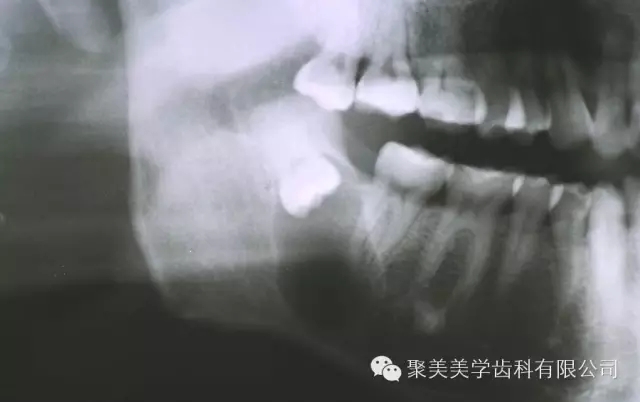

阻生牙不拔,形成囊腫!

放大看!

640.webp.jpg